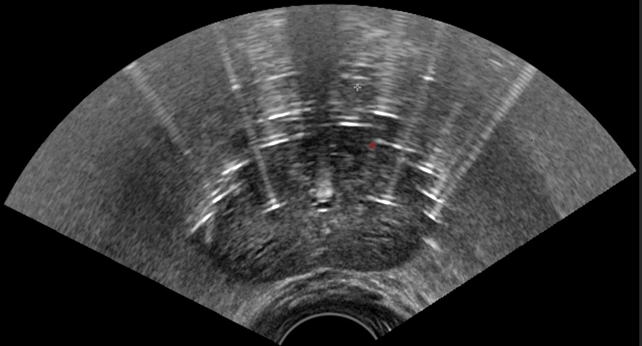

エコーを用いてシードを留置している様子

前立腺内の線量分布の確認